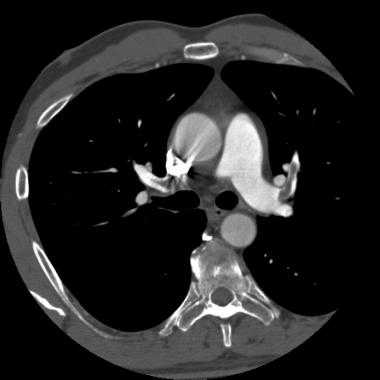

Спиральная КТ с контрастным усилением позволяет законтрастировать просвет легочных сосудов и увидеть тромб в их просвете. У молодого мужчины после межконтинентального перелета возникла острая боль в груди и нарушение дыхания. КТ визуализирует тромб в артерии переднего сегмента верхней доли левого легкого ( LA 2) и артерии переднего сегмента верхней доли правого легкого ( RA 2).